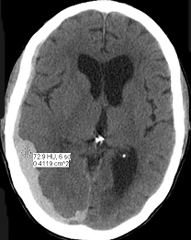

Non contrast CT head. Head CT showed a large crescenteric right-sided acute subdural hematoma.

NNNoncontrast CT

CT density of blood is 74 HU consitant with acute blood |

Diagnosis: Acute Subdural Hematoma

- Head CT showed a large crescenteric right-sided acute subdural hematoma.

- Acute subdural hematoma covering the right cerebral hemisphere (arrows), more prominent posteriorly.